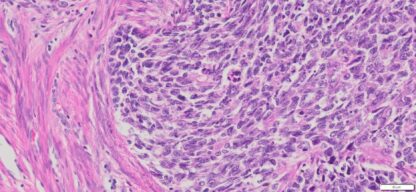

Description

| Organ& Tissue | Pathology Diagnosis | Gender/Age | % Tumor Area | Grade | TMN Stage | Biomarkers |

| Endometrial | Endometrial carcinosarcoma (malignant mixed Müllerian tumor) | Female/52 | 40% | NA | pT3apN1Mx | MLH1-2,MLH6 and PMS2: Intact nuclear expression |

More Images of H&E Stain and IHC